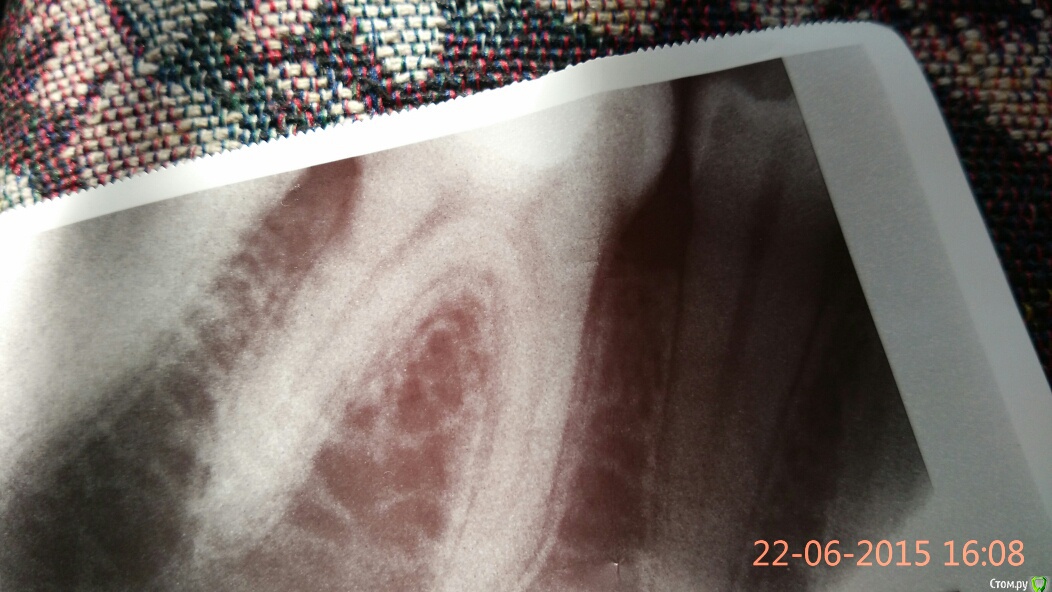

aleksei_sataev Опубликовано 22 июня, 2015 Поделиться Опубликовано 22 июня, 2015 Беспокоит зуб при накусывании одномоментно, неделю назад в гос.поликлиники за деньги пломбировал 36 зуб(кариес), прокомментируйте снимок. Нервы теперь удалять? До обращения зуб не болел, просто решил кариес весь вылечить. Ссылка на комментарий

St. Опубликовано 22 июня, 2015 Поделиться Опубликовано 22 июня, 2015 стоматолог сказал, что нервы удалять 100%, Пломба действительно по снимку близко к нерву, но я бы рекомендовала все-таки сначала понаблюдать. 1 Ссылка на комментарий